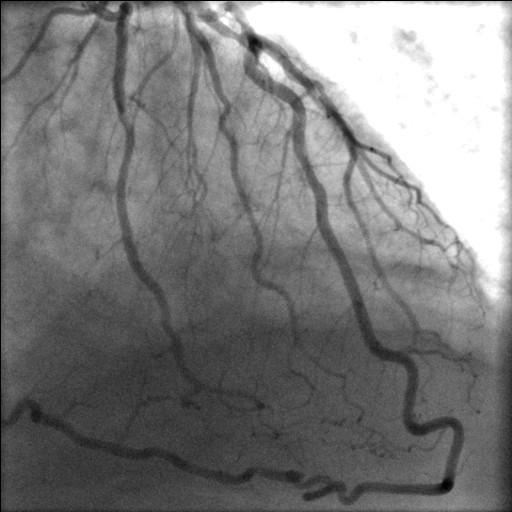

We describe, in a 61 year old man, with coexistent aortic stenosis, the anomalous origin of posterior descending artery (PDA) from a stenotic left anterior descending (LAD) artery, as its continuation across the left ventricular apex, in the presence of a normally arising and atretic proximal right coronary artery. The patient underwent mechanical aortic valve replacement and triple coronary artery bypass grafting and made an uneventful recovery. To the best of our knowledge, origin of PDA as a continuation of LAD across the left ventricular apex in the presence of a normally arising but atretic proximal right coronary artery has never been described in literature before. There is one previous case report of continuation of LAD as PDA across the left ventricular apex in a patient with single left coronary coronary artery with an absent right coronary ostium. As the blood supply to the entire interventricular septum is derived from this "hyperdominant" LAD system, stenosis of LAD can be catastrophic. A review of literature of the anomalies of right coronary artery and, in particular, of its anomalous origin from LAD and its coexistence with aortic stenosis, is presented.

我们描述了一名61岁患有主动脉瓣狭窄的男性患者,其右冠状动脉近端正常起源但闭锁,后降支动脉(PDA)异常起源于狭窄的左前降支动脉(LAD),并作为其延续穿过左心室心尖。该患者接受了机械主动脉瓣置换术和三支冠状动脉搭桥术,术后恢复顺利。据我们所知,在右冠状动脉近端正常起源但闭锁的情况下,PDA作为LAD的延续穿过左心室心尖的情况此前从未在文献中被描述过。之前有一例关于单支左冠状动脉且无右冠状动脉开口的患者中,LAD作为PDA延续穿过左心室心尖的病例报告。由于整个室间隔的血液供应都来自这个“优势过强”的LAD系统,LAD狭窄可能是灾难性的。本文对右冠状动脉异常,特别是其起源于LAD及其与主动脉瓣狭窄并存的文献进行了综述。